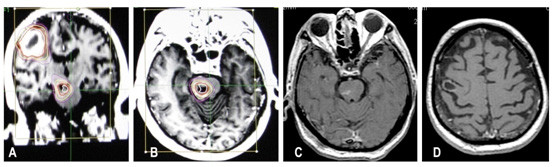

脑干转移瘤:脑干转移瘤占颅内转移瘤的3%左右,但是却严重威胁患者的生命。伽玛刀和常规放疗对脑干转移瘤有较好的控制作用,但是,照射剂量高容易出现脑干水肿,症状加重,照射剂量低,肿瘤控制不佳。射波刀低分割照射,既可以提高照射肿瘤的剂量又可以减轻脑干水肿,治疗后患者症状逐渐改善,脑干转移瘤肿瘤缩小或消失。如图8所示

图8:肺癌患者,脑干和右顶叶多发转移瘤。A和B:射波刀治疗计划;C和D射波刀分次治疗后3个月,肿瘤几乎消失,患者原有症状消失。

5、神经系统以外肿瘤的射波刀治疗:射波刀除了治疗神经系统肿瘤和血管畸形外,目前它主要应用于全身肿瘤的放射外科治疗。根据文献报道,射波刀治疗的多数病例为神经系统以外的肿瘤。射波刀已广泛用于肺癌(如图11)、肝脏肿瘤、肾脏肿瘤、前列腺癌、骨肿瘤和一些妇科肿瘤的放射治疗。

图10:肝癌脊柱转移,患者疼痛症状明显。A: 射波刀治疗前,PET-CT显示腰1椎根和腰3锥体转移瘤; 射波治疗后一周,疼痛症状消失。B: 射波刀治疗后1月复查PET-CT显示转移瘤病灶的FDG(葡萄糖)摄取变为正常。

图11:晚期肺腺癌患者,因脑部转移瘤行开颅手术,病理诊断为腺癌,肺CT检查发现肺癌,然后射波刀治疗。A、B和C:射波刀治疗前肺部CT, A为水平位,B: 为冠状位,C:为矢状位,图像中的红色曲线为治疗时的等剂量曲线。照射3次,每天1次,每次12Gy。DE:治疗后2月,肿瘤缩小为小的结节。FG: 治疗后5个月,肿瘤几乎消失;HIJ: 治疗后7个月,肿瘤消失。